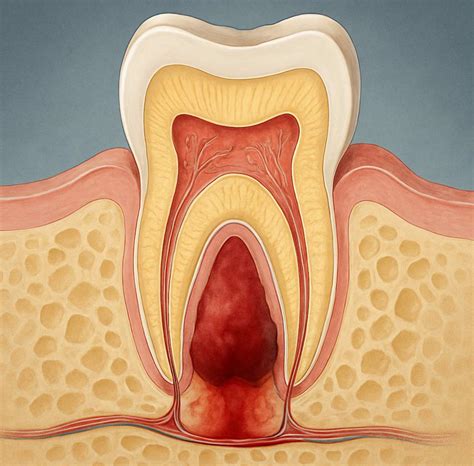

The development of an abscess is a progressive process. It begins with bacteria entering the tooth pulp through a cavity, crack, or chip, leading to inflammation and eventual infection. As the infection progresses, it advances through distinct phases, each characterized by worsening symptoms and increased risk to your overall health. Recognizing these tooth abscess stages allows you to act quickly.

• Bacterial Entry: Bacteria enter through a break in the tooth enamel.

• Pulpitis: The inner pulp of the tooth becomes inflamed, causing sensitivity.

• Infection and Pus Formation: As the pulp dies, an abscess forms at the root tip or gum line.

• Spreading Infection: If untreated, the infection spreads to the surrounding bone and soft tissues of the face or neck.